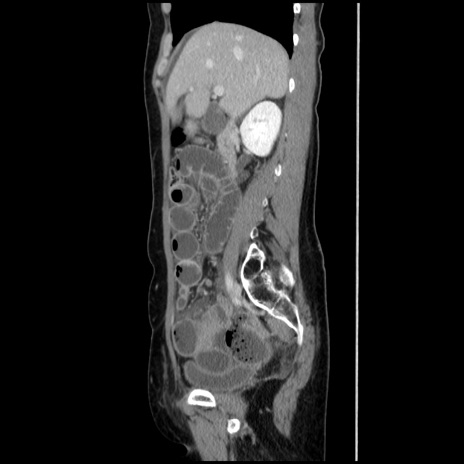

【症例】40歳代 女性

【主訴】上腹部痛、嘔気・嘔吐

【現病歴】約9時間前頃から急に上腹部痛、嘔気、嘔吐が出現。改善しないため救急要請。

【既往歴】子宮頚癌(広汎子宮全摘術、放射線療法)、腸閉塞

【身体所見】腹部:平坦、軟、腸雑音亢進、上腹部を中心に腹部全体に圧痛あり。

【データ】WBC 8400、CRP 0.03

冠状断像